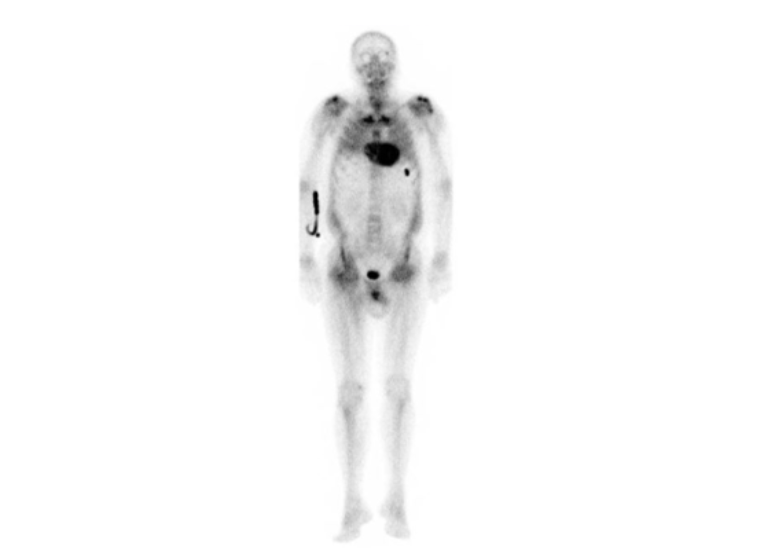

• Ganzkörper-SPECT/CT zur Knochenszintigraphie (99mTc-DPD): starke Fixierung des Radiopharmakons mit besonderer Beteiligung der septalen und lateralen Regionen der linken Herzkammer, verbunden mit einer Fixierung in der rechten Herzkammer und einer deutlichen globalen Reduktion der Aufnahme im Skelettbereich (Perugini-Score: 3).

Knochenszintigraphie mit Perugini-Score Grad 3

Die endgültige Diagnose erfordert eine histologische Bestätigung des Vorhandenseins von Amyloid-Substanz in Biopsieproben aus Geweben, die an dem infiltrativen Prozess beteiligt sind. In jüngster Zeit hat die nukleare Bildgebung die Diagnose der ATTR-Amyloidose revolutioniert. Knochenspezifische Radioisotope, die bei der Ganzkörper-Knochenszintigraphie verwendet werden, binden Transthyretin-Amyloid-Ablagerungen. Der Grad der myokardialen Akkumulation ist variabel und wird visuell durch den Perugini-Score bestimmt (von 0 = keine Akkumulation bis 3 = pathologische myokardiale Akkumulation, größer als die Knochenakkumulation). Bei Patienten mit einem Score von 2 bis 3 ist bei Fehlen von Laboranzeichen, die auf eine AL-Amyloidose hindeuten, die nicht-invasive Diagnose einer ATTR-Amyloidose mit einer Spezifität und Sensitivität von über 99 Prozent möglich. Eine anschließende genetische Analyse ermöglicht die Unterscheidung zwischen Mutanten und Wildtypen.